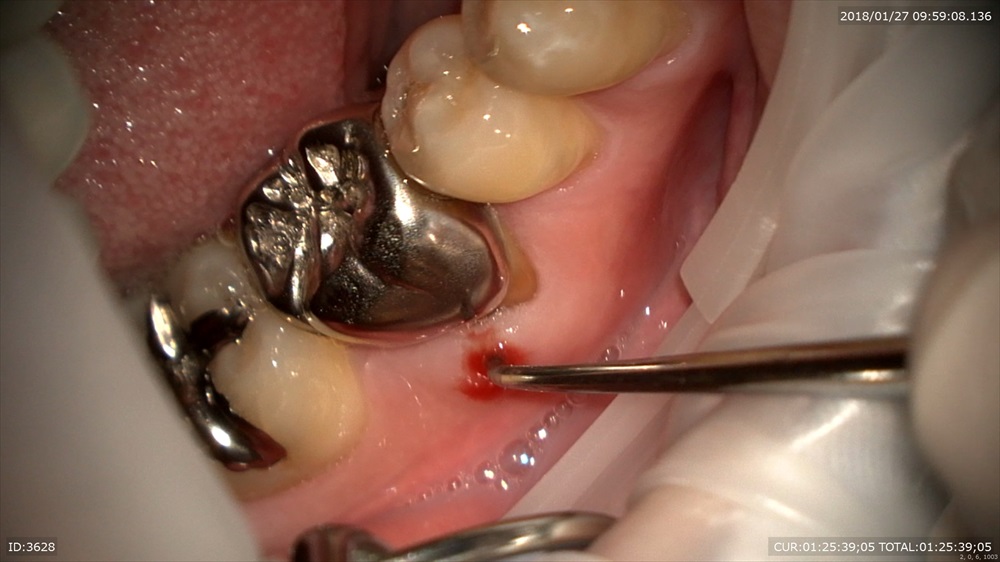

今日の患者さん。この方は他院の根管治療後腫れて治らず今年の年始にいらして頂きました。

歯科ドックの結果

歯周病治療、根管治療、土台、被せ物のやり直しが必要でした。

細かく根管治療

手間ヒマかけて

23倍でバイオフィルムを取り

土台をたて

仮歯で半年様子見